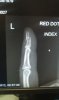

Ambulance, police and 6 hours later an amazing save with leather (thank you leathers). 6 hours sitting in my own A&E with colleagues caring for you is fun (accident only 100 m from work entrance). Managed to score many sprains/strains to left side upper body from being slammed by her side mirror and a displaced fractured finger requiring surgery, 6 weeks off work and no biking for longer :(

That is an impressively delicate fracture!

I was going for something petite like that, just don't have the finenesse apparently.

Bike is safe, priorities first :thumbsup: